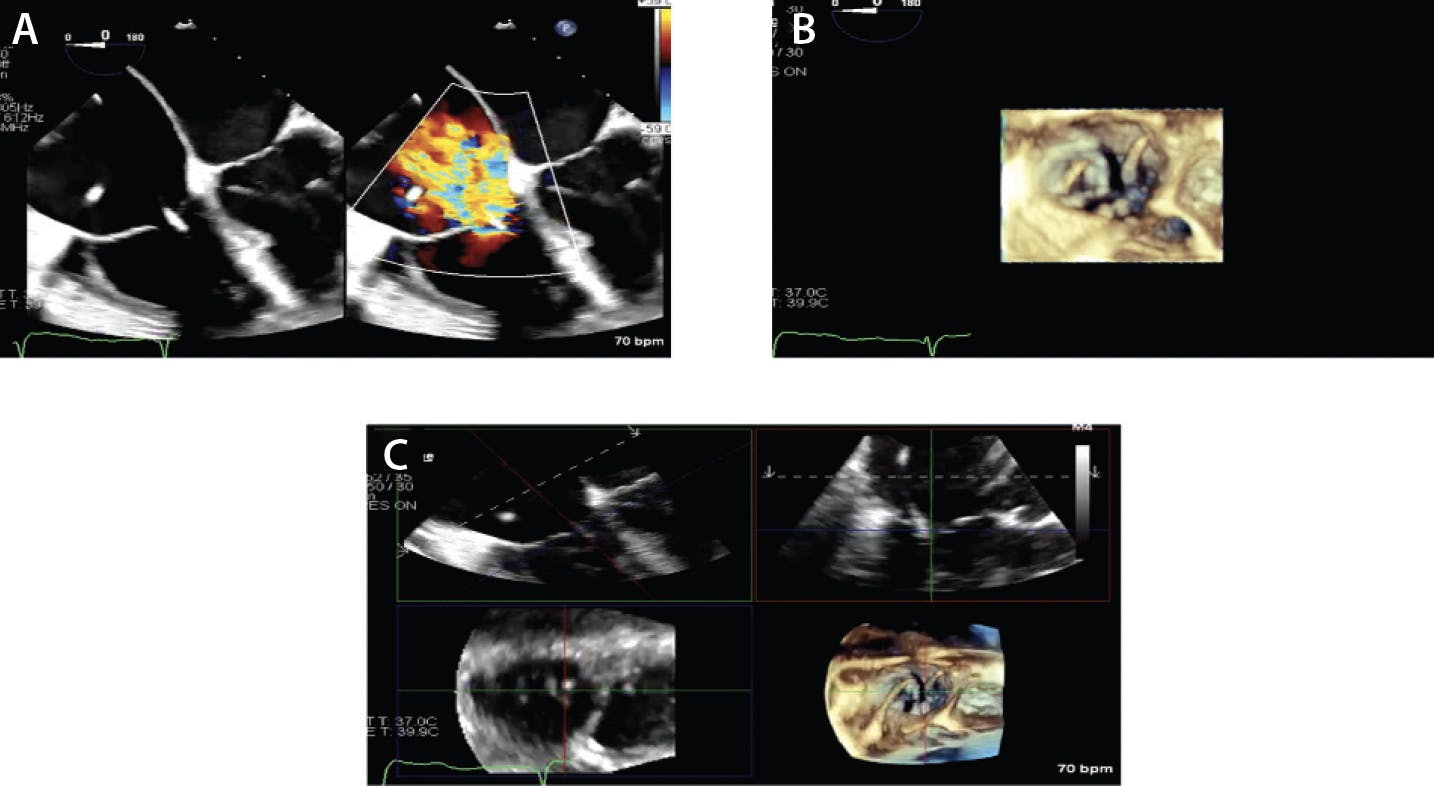

Figure 1. A 0° midesophageal TEE view with and without color Doppler and severe TR where the jets splay out into the right atrium (A). Three-dimensional views of the tricuspid valve with and without color Doppler where there is a coaptation defect centrally (B, C). A, anterior leaflet; AoV, aortic valve; MV, mitral valve; P, posterior leaflet; S, septal leaflet.

TEE is fundamental in the preprocedural assessment of patients undergoing TTVI. It provides detailed, high-resolution images of the tricuspid valve and its surrounding structures, which are critical for planning the intervention. Given the complexity of the tricuspid valve, detailed anatomic information must be obtained, including the morphology of the tricuspid leaflets, the size and shape of the annulus, and the degree of annular dilation. In addition, other features such as right ventricular (RV) function, leaflet prolapse, coaptation gaps, and presence of any thrombi or vegetation should be noted because these can influence device selection and procedural strategy (Figure 1).1 Quantification of TR is also essential and should be routinely performed on transthoracic echocardiography and TEE.